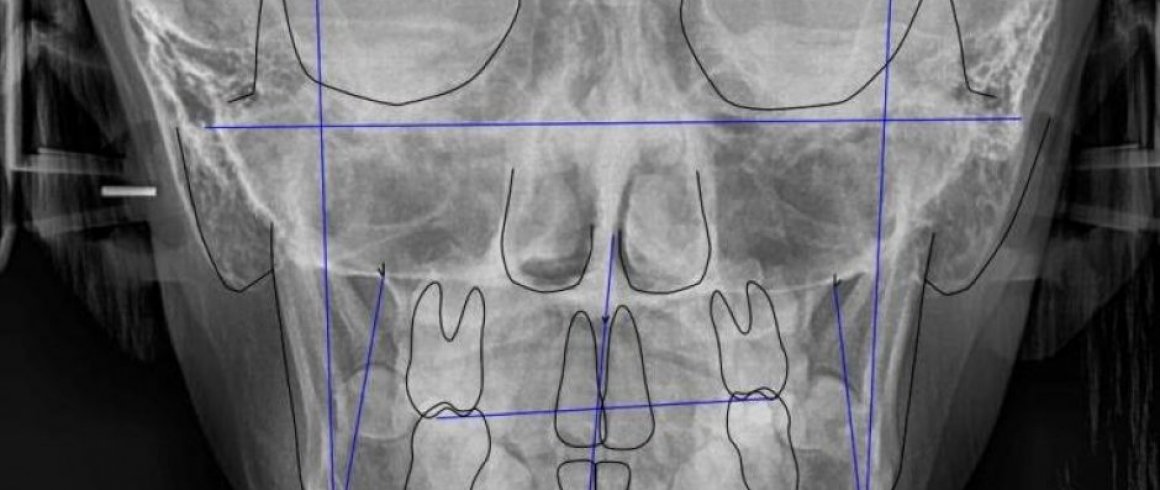

- Análisis Cefalométrico Frontal

- Documentación Ortodontica

- Análisis Cefalométrico Lateral